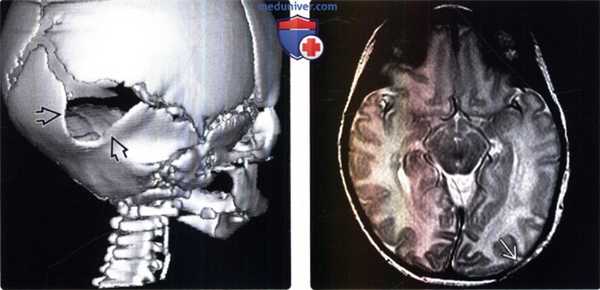

(Слева) КТ в костном режиме, корональная косая 3D реконструкция свода черепа: у пациента с врожденной фокальной аплазией волосистой части кожи головы определяется крупный дефект свода черепа, переходящий в лямбдовидный шов. Дефект расположен в области, смежной с зоной аплазии кожи.

(Справа) МРТ, Т2-ВИ, аксиальный срез: у этого же пациента с врожденной фокальной аплазией кожи и дефектом левых отделов затылочной кости (компонента свода черепа) определяется истончение подкожной жировой клетчатки в сочетании с интактной твердой мозговой оболочкой на уровне тотчас ниже участка аплазии кожи.